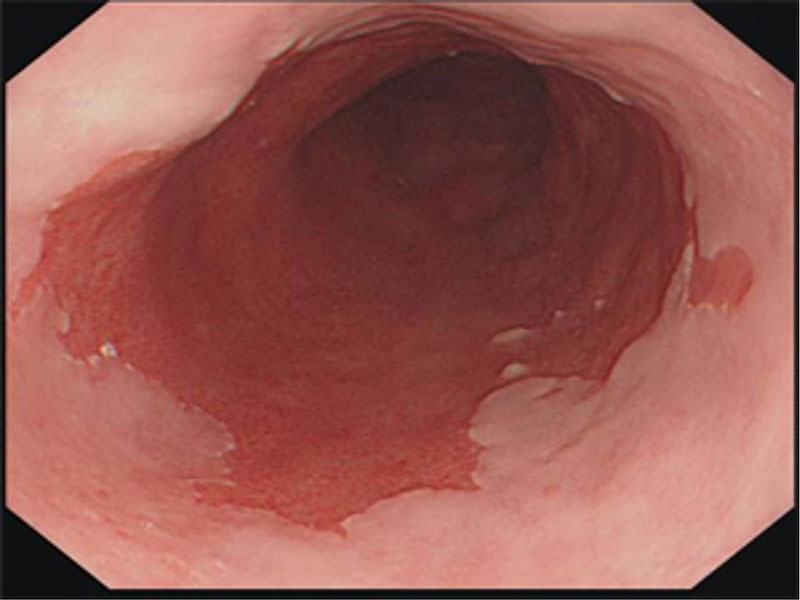

Endoskopide Reflü ile İlgili Ne Görülür?

Reflünün sindirim sisteminde yarattığı hasarı görmenin en kesin yolu endoskopidir. Yemek borusuna kaçan asit hasar yarattıysa bunu görebiliriz.

Yemek Borusu Barrett Hastalığı

Uzun süreli reflü hastalarında ortaya çıkan Barrett Hastalığını, ancak endoskopi sırasında aldığımız doku örnekleri ile ayırt edebiliriz. Mide fıtıklarını görmenin ve kanıtlamanın en doğru yolu da endoskopidir.

Yüksek çözünürlük (HD) en yeni kuşak cihazlarda mevcuttur. Dokuları daha iyi görmeyi ve ayrıntıları yakalamayı sağlar. Narrow Band Imaging (NBI) ise normal ışık dalga boylarını değiştirerek görüntü elde etmeyi sağlar; NBI ile daha derinlemesine görüntü elde edilir.